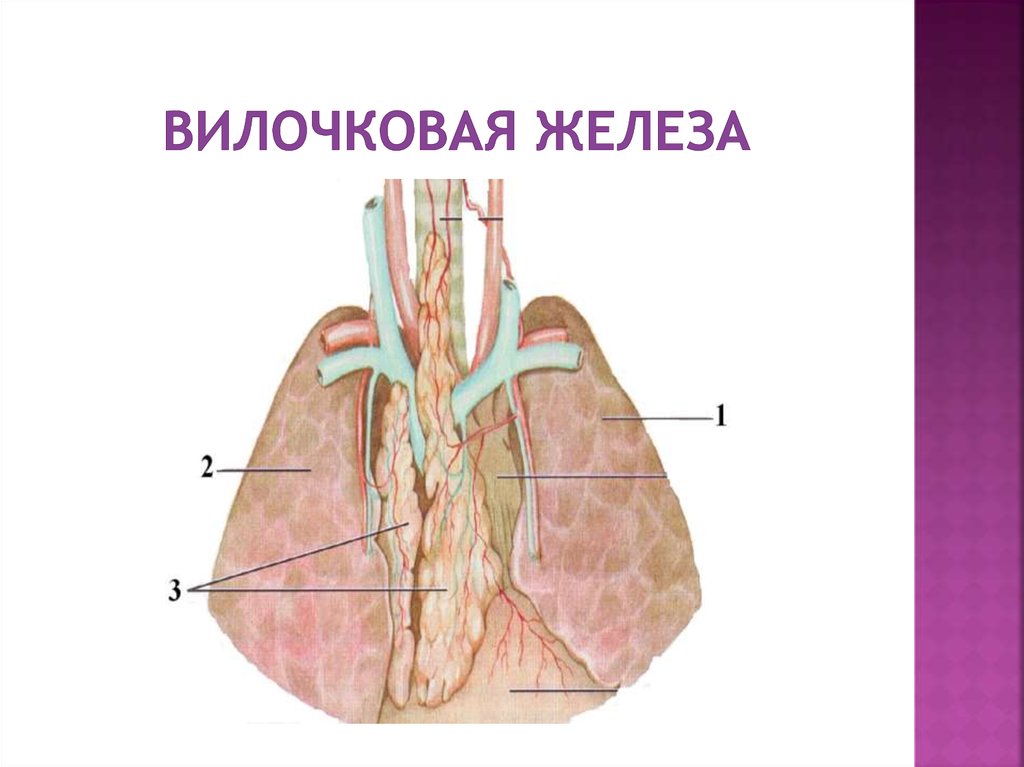

Фотографии вилочковой железы тимуса: структура и функции